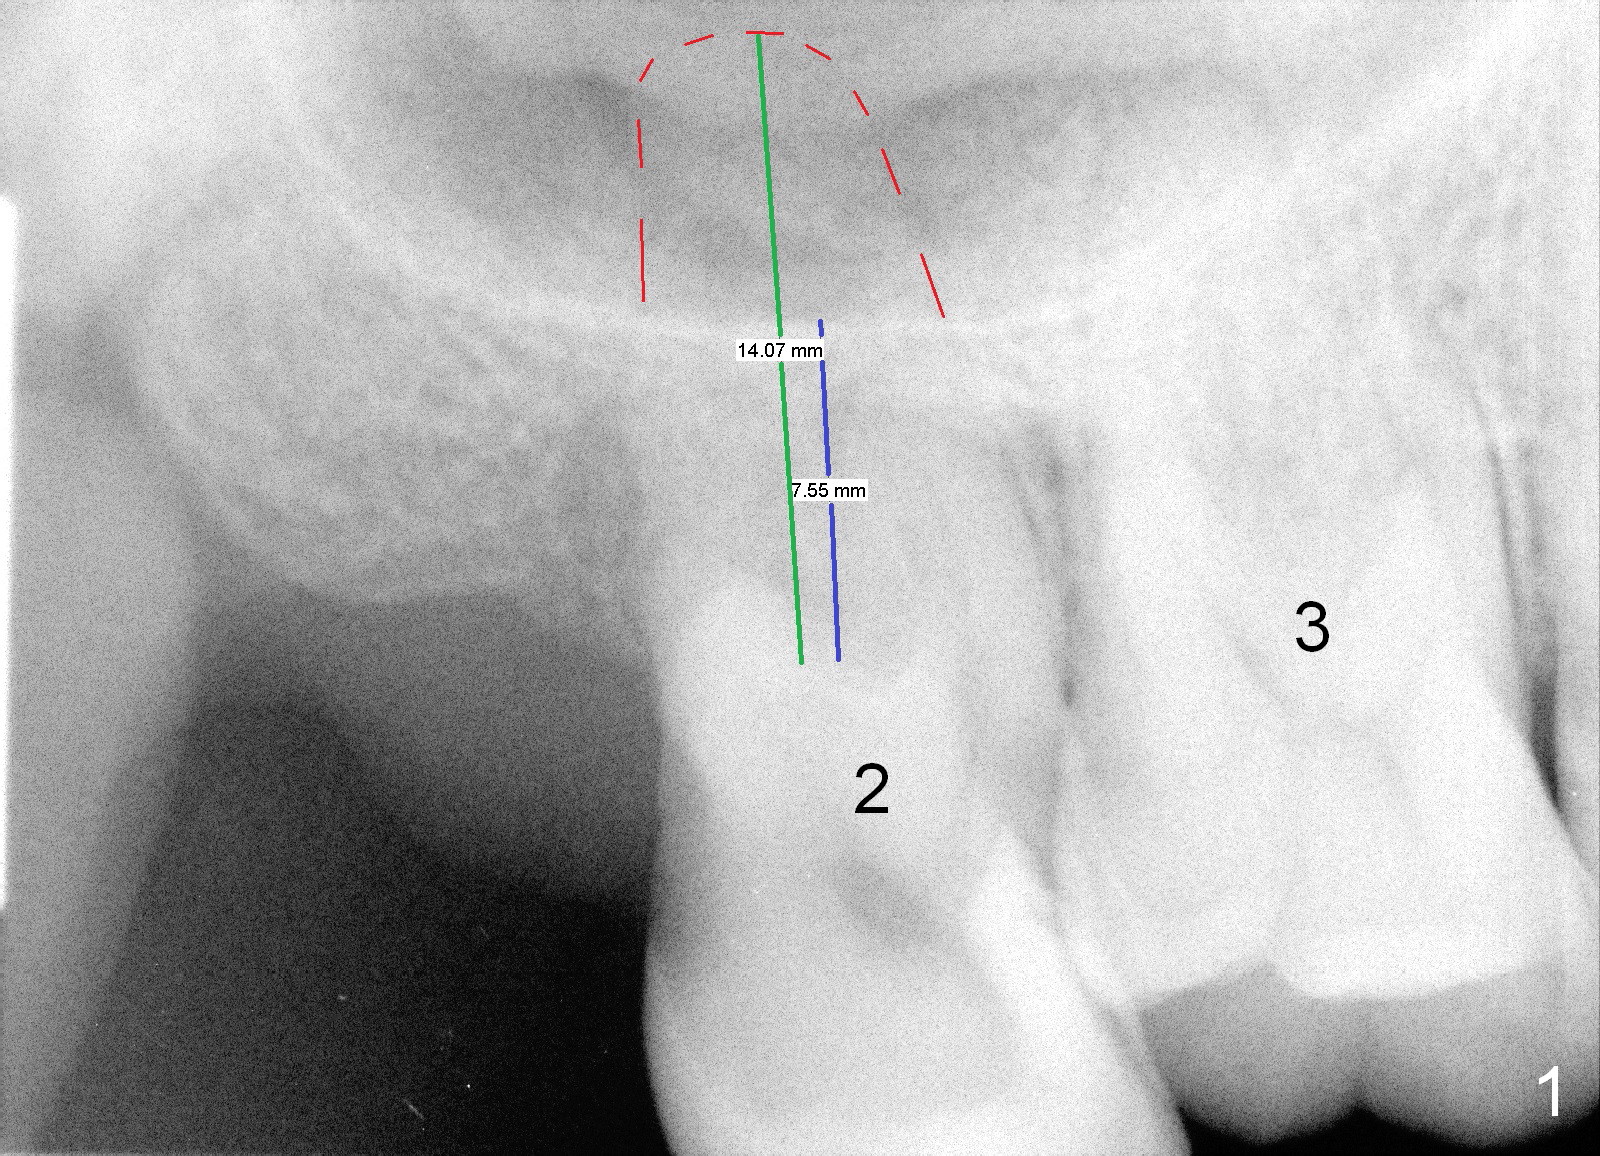

LJ will return for #2 implant placement 2 months post #31 implant placement.  Fig.1 was taken 2 years ago.  The tooth #2 had been supraerupted.  The bone height is apparently 7.5 mm (blue line), but with proper manipulation, there would be 14 mm bone available (green line) for placement of an immediate implant.  Fig.2 was taken a year post extraction.  The bone height is reduced to 6 mm (blue line).  With sinus lift, a 8 mm bone-level implant will be placed.